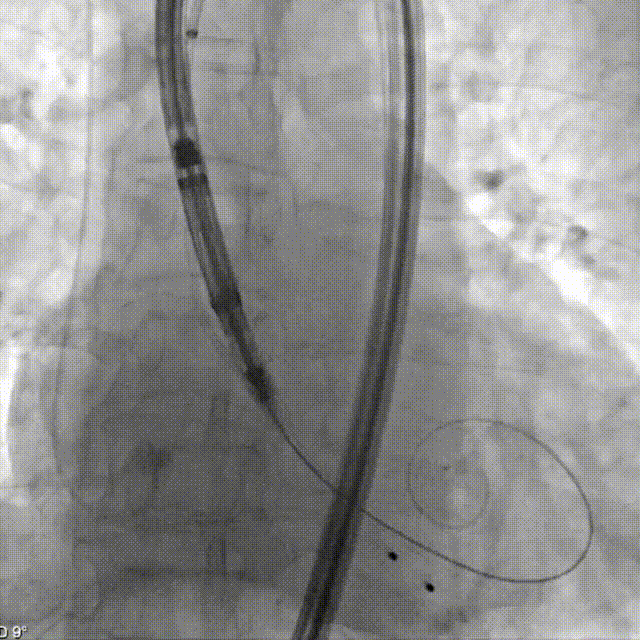

定位键展开

瓣膜同轴调整

患者深度镇静后超声引导下建立入路,跨瓣后左室放置预塑形导丝,使用TaurusTrio系统定制的等效于18F超长导引鞘定位STJ。输送系统装载THV27瓣膜,在大鞘保护下从右股动脉送入,安全通过降主动脉及钙化弓顶。在右窦中心位下,回撤导引鞘远端至降主动脉后定位键展开,使用调弯功能改善瓣膜同轴性,DSA下观察THV从大弯侧调至居中,再通过旋转定位手柄在右窦中心位下调整三个定位键与原生窦一一对齐,后推进THV使定位键进入窦底,实现Commissural alignment,通过造影依次确认无、右、左窦内定位键及深度后,最终脱钩释放。术后即刻超声心动图评估显示瓣膜位置良好,无瓣周漏,无中心反流,血流动力学指标优异。